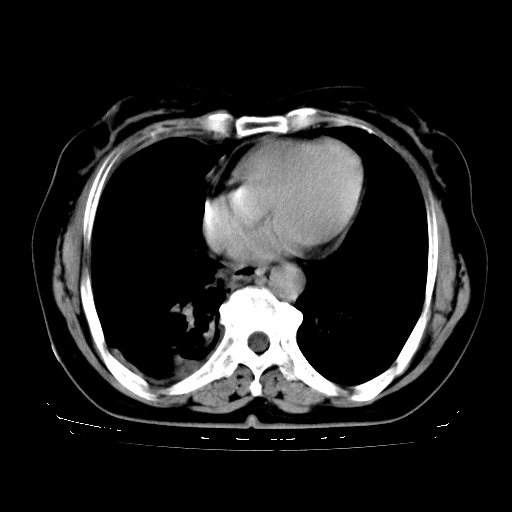

以下是引用zhangzhongshou在2008-3-22 12:52:00的发言:[br]1、右侧液气胸。[br]2、腹水。建议进一步检查。

以下是引用鲁巨ct在2008-3-22 14:10:00的发言:[br]1、右侧液气胸,右中下叶节段性不张。[br]2、腹水,建议上腹部ct检查

以下是引用zjzjr在2008-3-22 17:19:00的发言:[br]1、右侧液气胸,右下叶节段性不张。[br]2、腹水,建议上腹部ct检查